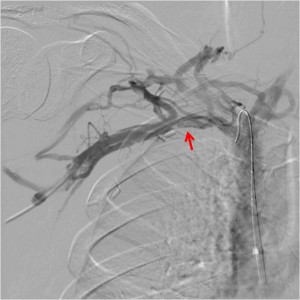

When a patient presents with an acute clot, imaging is usually done with duplex ultrasound. It is a highly sensitive test in experienced hands. Acutely, you will find a subclavian vein thrombus that will often extend to the axillary vein:

Venography is recommended in two instances. First, if the diagnosis is suspected, but proof was not obtained otherwise. For instance, when the duplex is inconclusive. The second use for venography, of course, is during a procedure. Venography often reveals venous collaterals, suggesting chronic sub-total compressions have been present. Furthermore, venography can be performed when the hand is in the neutral position or abducted. If extrinsic compression is visible, that suggests Paget Schroetter. Surprisingly CT and MR are not well suited imaging modalities for diagnosing Paget Schroetter, despite their obvious capabilities in diagnosing clot per se.